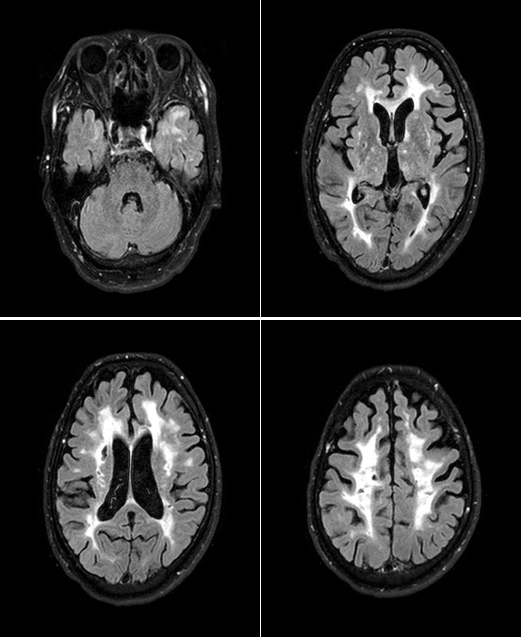

CALADIS

白く写っている箇所に白質病変、黒く点状・癒合状に抜けているところにラクナ梗塞が起きている  水野敏樹先生ご提供

上図のMRI画像をご覧いただくと、CADASILの白質病変は眼球の後ろ側の側頭極(そくとうきょく)という部分から起こりやすいことが特徴です。

近年は、医師のあいだでも、「側頭極に白質病変を確認したらCADASILを疑う」という認識が浸透してきたため、比較的早期にCADASILを診断できるようになってきました。

CADASSII

脳梗塞未発症の患者さんのMRI画像 水野敏樹先生ご提供

上の写真は70代女性のCADASIL患者さんのMRI画像です。白質が真っ白に傷ついてしまっていて、白質病変はかなり進行してしまっていますが、脳梗塞は発症していないのです。白質病変と脳梗塞は異なる現象ですから、脳梗塞に引き続き起こるような麻痺などの運動機能障害や気分障害、認知症などの症状はなく、現在も元気に主婦として仕事をされています。